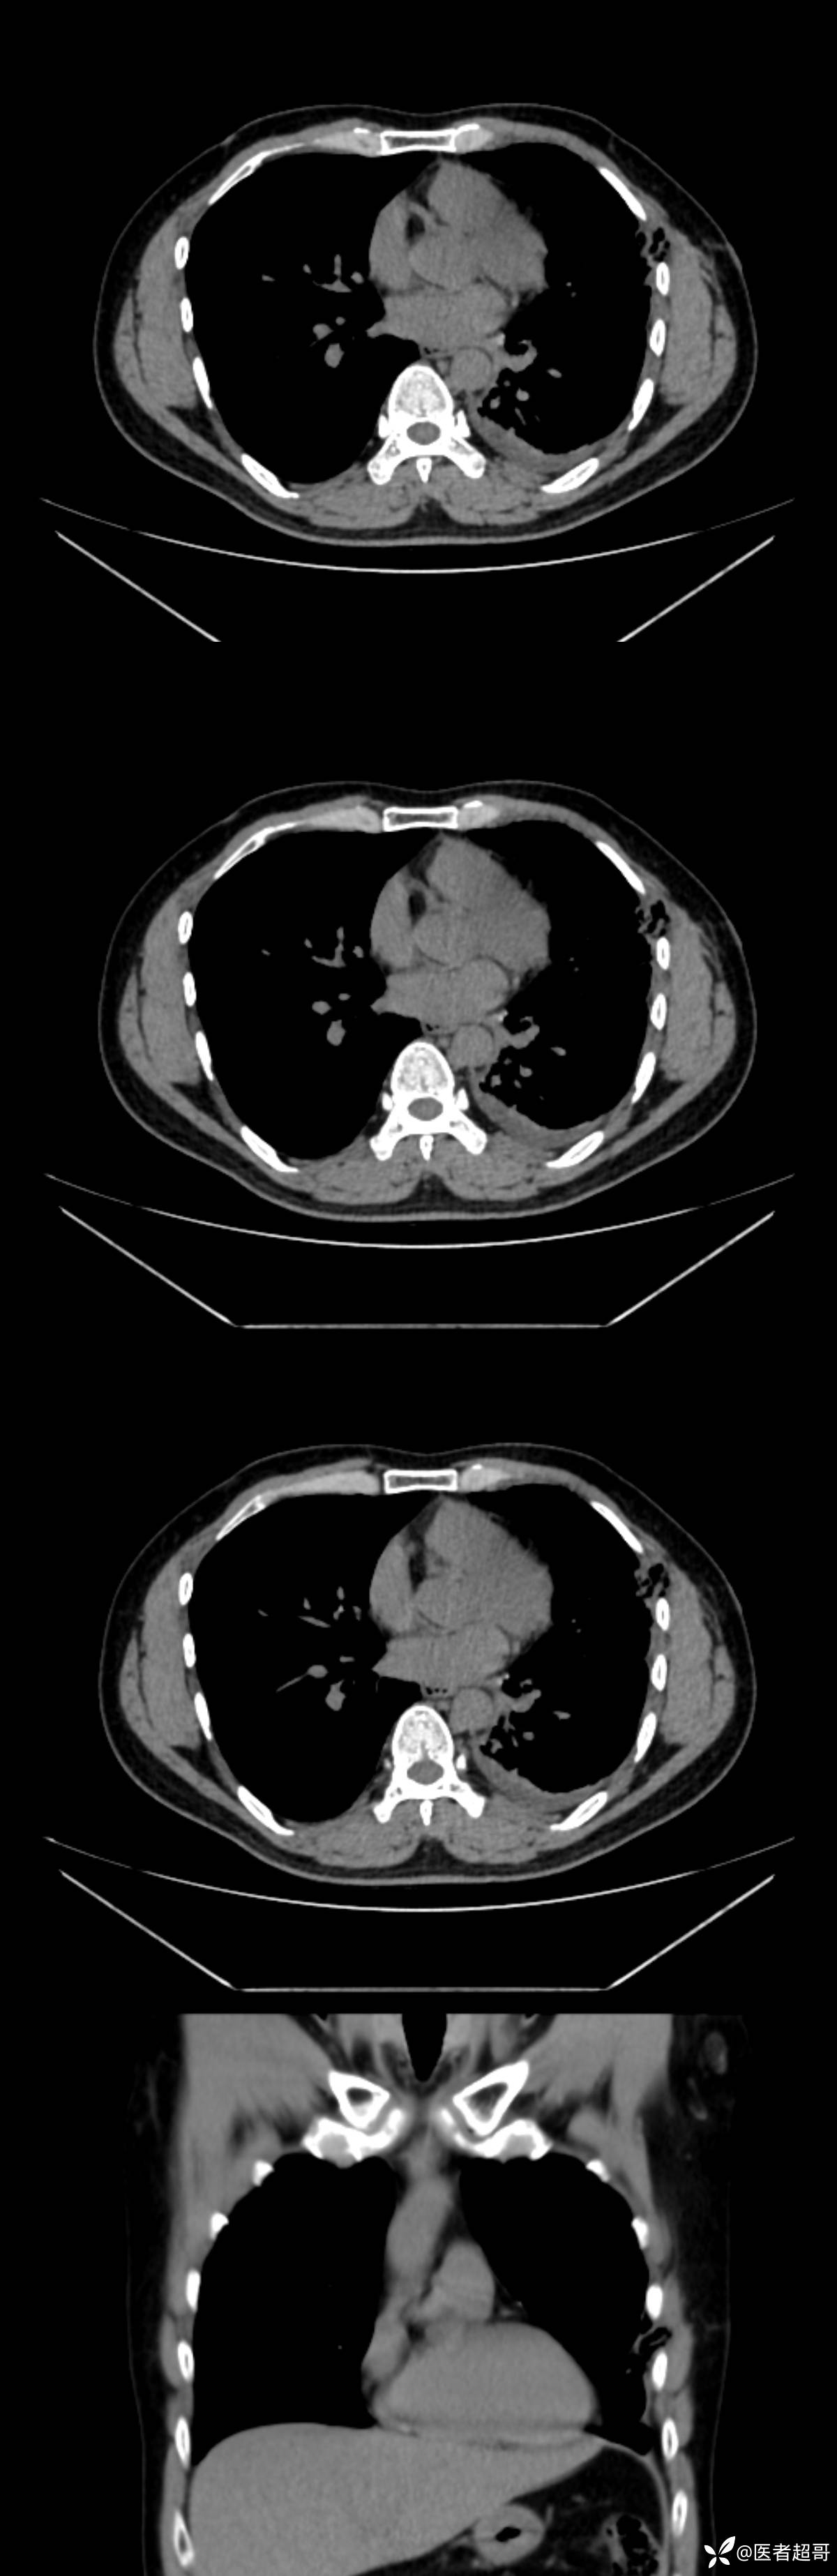

男38岁,胸痛

既往病史:患者自诉无明显诱因出现左侧胸部疼痛1天,无发热、咳嗽,无胸闷咳嗽,主诉:左侧胸部疼痛1天 体格检查:神清,胸廓无畸形,左侧胸壁轻触痛